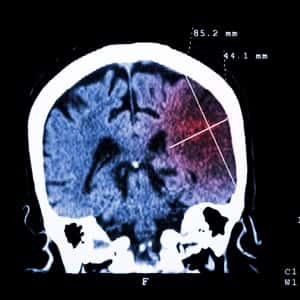

People who experience a transient ischemic attack, also known as a TIA or a minor stroke, are at a significantly increased risk for another blood clot in the brain. In a TIA, the clot resolves on its own without causing lasting damage. But a persistent clot in the brain makes for an ischemic (pronounced iss-KEE-mik) stroke. The consequences can be devastating. As a result, doctors often prescribe anticlotting drugs such as rivaroxaban (Xarelto), clopidogrel (Plavix) or aspirin to prevent stroke.